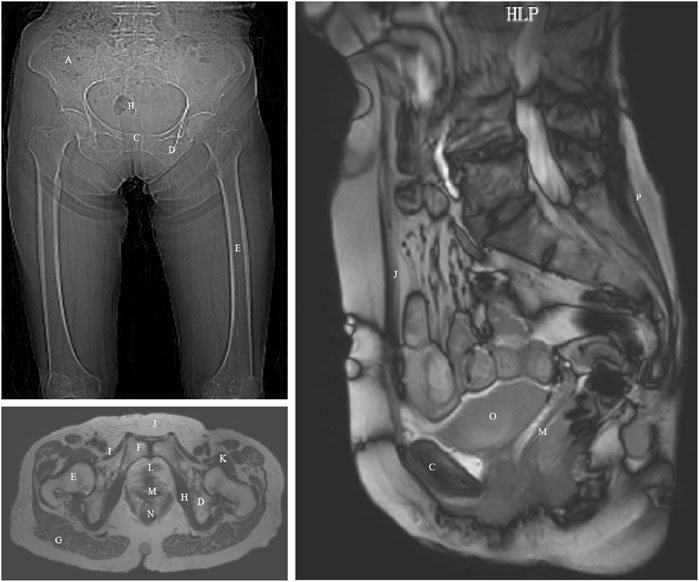

Objective: This study aims to utilize finite element analysis (FEA) to explore the effects of different rehabilitation training methods on the ability of elderly women to maintain urinary and fecal control. It also seeks to determine the muscle prioritization during pelvic rehabilitation training, providing a scientific basis for personalized rehabilitation nursing. Methods: A 3D pelvic-thigh modeling was constructed based on CT and MRI images from a 70-year-old Chinese elderly female volunteer. Model validity was verified by assessing relative changes in waist circumference, RVA, and ARA against imaging measurements, with geometric deviations controlled within 10%. The material properties of the muscles were altered to simulate the effects of five different physical rehabilitation methods. By comparing changes in the retrovesical angle (RVA) and anorectal angulation (ARA) under different muscle material properties settings, the relationship between rehabilitation training methods and urinary and fecal control was quantified. Results: The constructed model demonstrated high geometric consistency with pelvic floor anatomy, showing less than 8.28% deviation from imaging-based measurements. As muscle material properties improved, the RVA gradually decreased, and the ARA gradually increased, approaching normal ranges. The results highlight the critical roles of the levator ani, pelvic floor, rectus abdominis, erector spinae, and hip muscles. Conclusions: The findings from this simulation indicate the potential efficacy of rehabilitation training in supporting urinary and fecal control. The study emphasizes the importance of personalized pelvic floor rehabilitation programs based on gender differences, muscle status, and dysfunction types, offering new perspectives and possibilities for using FEA in elderly populations. Nevertheless, the findings are derived from a single-subject model and computational simulations without direct clinical validation, which may limit generalizability.